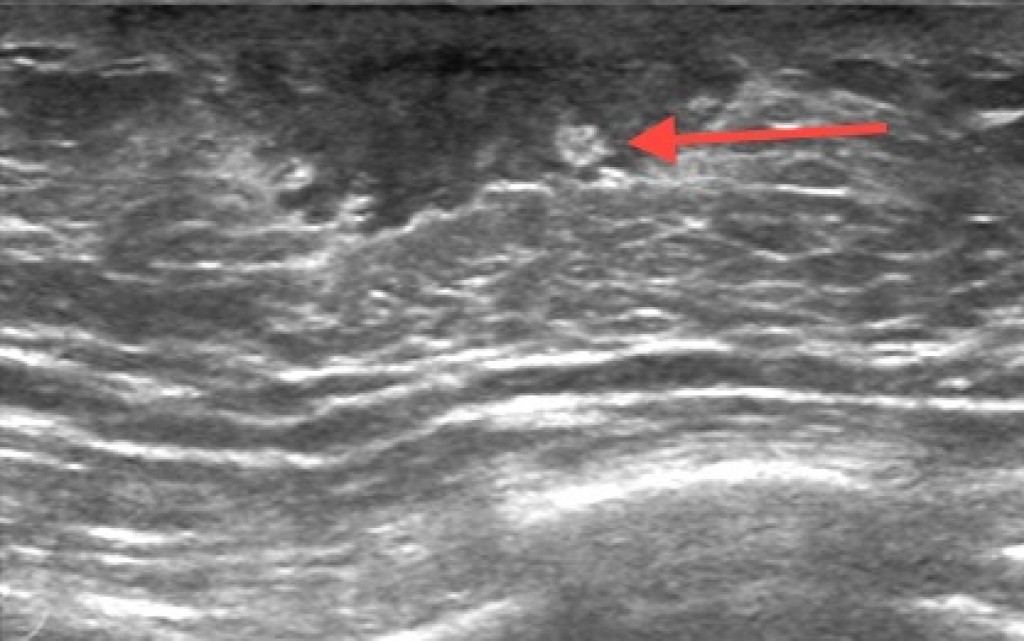

Данное состояние часто связано с относительным или абсолютным преобладанием женских половых гормонов (эстрогенов) над мужскими. Диагностика заболевания включает обязательное УЗИ грудных желез для подтверждения наличия железистой ткани, а также комплексное лабораторное исследование уровня тестостерона, эстрадиола и пролактина. Важным этапом является поиск первопричины, которой могут быть заболевания печени, опухоли яичек или прием определенных лекарственных средств (анаболические стероиды, некоторые нейролептики). Скрининг у мужчин проводится при появлении уплотнений или болезненности в области соска. Профилактика заключается в отказе от вредных привычек, контроле веса и осторожном применении препаратов, влияющих на гормональный фон. Мужчины также могут болеть раком грудной железы, поэтому любые изменения в этой зоне требуют осмотра в кабинете маммолога. Медсестра должна проявлять деликатность при работе с такими пациентами, обеспечивая комфортные условия для обследования и забора анализов.